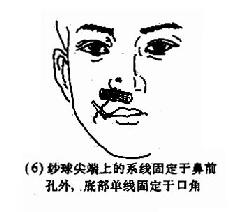

(2)后鼻孔填塞法(postnasal packing):先将凡士林纱条或消毒纱布卷迭成块形或圆锥形,长约3.5cm,直径约2.5cm,用粗线缝紧,两端各有约25cm长的双线,消毒备用。填塞时先收缩和表麻鼻腔粘膜,咽部亦喷有表面麻醉剂。用导尿管由前鼻孔沿鼻腔底部插入直达咽部,用镊子将导管从口腔拉出,导尿管尾端则留于前鼻孔外,再将填塞物上的双线系于导尿管,此时将填塞物由口腔送入鼻咽部,填塞于后鼻孔。为了减少患者痛苦,可用弯止血钳将填塞物在明视下送到悬壅垂的后上方,再将导尿管的鼻端向外拉紧。最后在前鼻孔处用一纱布球,将双线系于其上,以作固定,口腔端的线头可剪短留在口咽部,便于以后取出填塞物时作牵拉之用。后鼻孔填塞后,一般都需加行鼻腔填(图4-7)。鼻腔填塞物应于24~48小时内取出或更换,以防引起鼻窦及中耳感染等并发症。

图4-7 后鼻孔填塞法